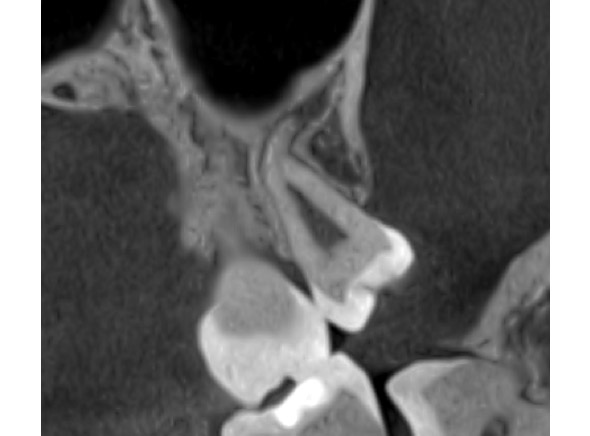

☆本院特別巨資增設 ”千萬級3D AI透視電腦斷層”,並配合“成骨膠原蛋白”施作 (上述兩項目前健保無給付),讓您遠離神經傷害、口鼻竇(炎)相通...等併發症,除健保之外,難免會有避免併發症風險的自費項目,網路上經常會有看到智齒拔完後唇麻、舌麻、口鼻竇相通等併發症,在本院嚴格自我要求下,此類併發症在本院幾乎趨近於零。